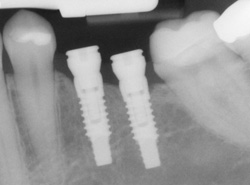

implants processAn implant is a new tooth made of steel and porcelain that looks just like your natural tooth. Your implant is composed of two parts that mimic a tooth's root and crown. The implant's "root" is a titanium steel rod placed into the jaw bone to act as a root. Once the rod is in place, a porcelain crown is attached to replace the top part of your tooth.